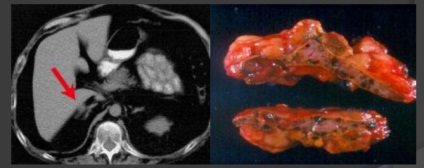

hemoragie suprarenală.

Nontraumatic (două sensuri. Stresul, diateza gemorragichesy, coagulopatie) și

Trauma (adesea numit dreapta. Blunt trauma cu leziuni la alte organe. ≈2% din toate leziunile. ≈26% au murit de traume severe).

DD :. adenoame, mielolipomy, feohr. mts, carcinom.

CT. Periph. câștig. 50-90 HU, scade treptat. Calcifiere poate fi singurul simptom rezidual.